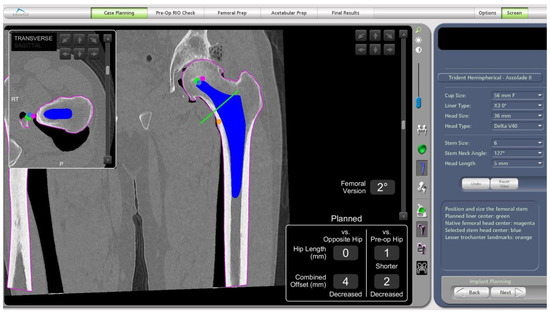

- In this case, the native femoral retroversion (−6 degrees) posed a challenge in avoiding impingement (Figure 7). Upon assessing VROM, bone-on-bone and implant-on-implant impingement in deep flexion were noted (Figure 8). Using the robotic software, the planned femoral version was corrected to +16 in the femoral broach (Figure 9a,b).

- The robotic software also enables preoperative and intraoperative visualisation of the anticipated postoperative X-rays accounting for any changes to the plan. In addition, the software allows for calculation of changes to the leg length offset compared to the preoperative and contralateral hips. In this case, the leg length was 1 mm longer compared to the opposite hip, and the combined offset was 6 mm increased compared to that preoperatively (Figure 12a,b).